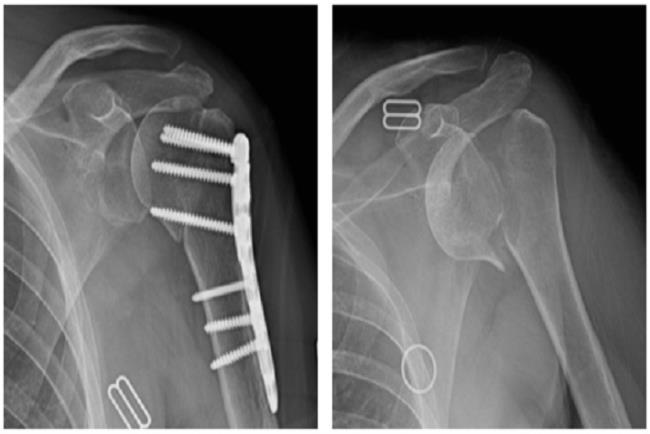

שבר מורכב בראש עצם הזרוע (בצילום מימין), שטופל ניתוחית בהחלפת כתף הפוכה (בצילום משמאל).